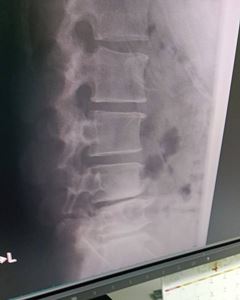

負傷・少林寺です🐷

4月が始まった

ばかりだと言うのに

約半年ぶりの

腰痛再発

腰・激痛⚡です!!